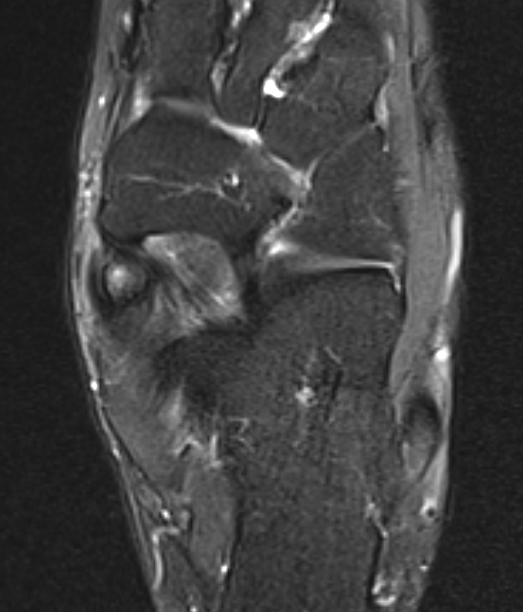

Bone Scan

MRI

Show edema about a symptomatic accessory navicular